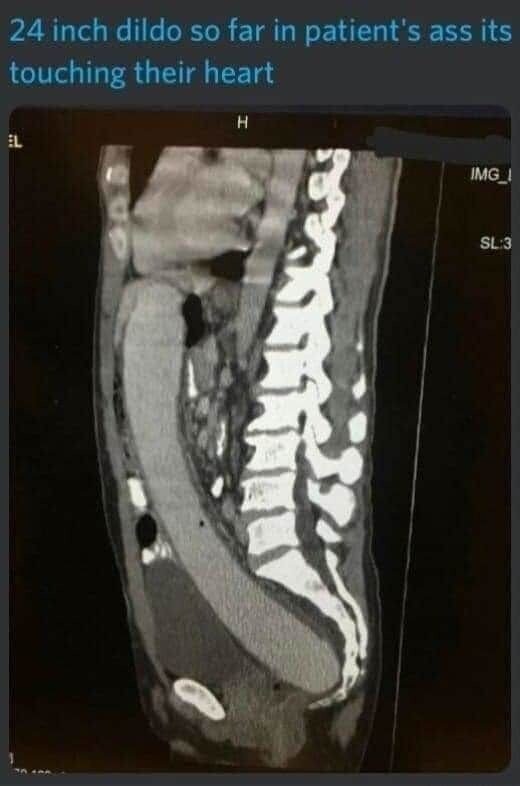

24인치 딜도가 안빠져서 병원온 사람의mri사진